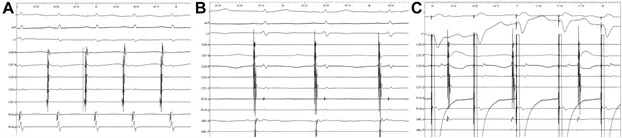

在完成左心耳定位后(图3A),将消融导管贴靠于最早激动点后,首先消融64秒,成功终止房速并转为窦性心律(见图4A和4B),随后在同一部位附近行巩固消融240秒。参数设置为温度43°C、功率20W、生理盐水灌注速度17 mL/min、接触压力不超过5~10 g(图2C)。

电生理检查显示,在右心室500 ms S1S1刺激时观察到室房分离(图4C)。心房刺激时,以400/350 ms进行右心房S1S2刺激可诱发心动过速,当S1S2为400/270 ms时出现108 ms的房室跳跃,提示存在房室结双径路。

图4 导管消融前后的电生理评估